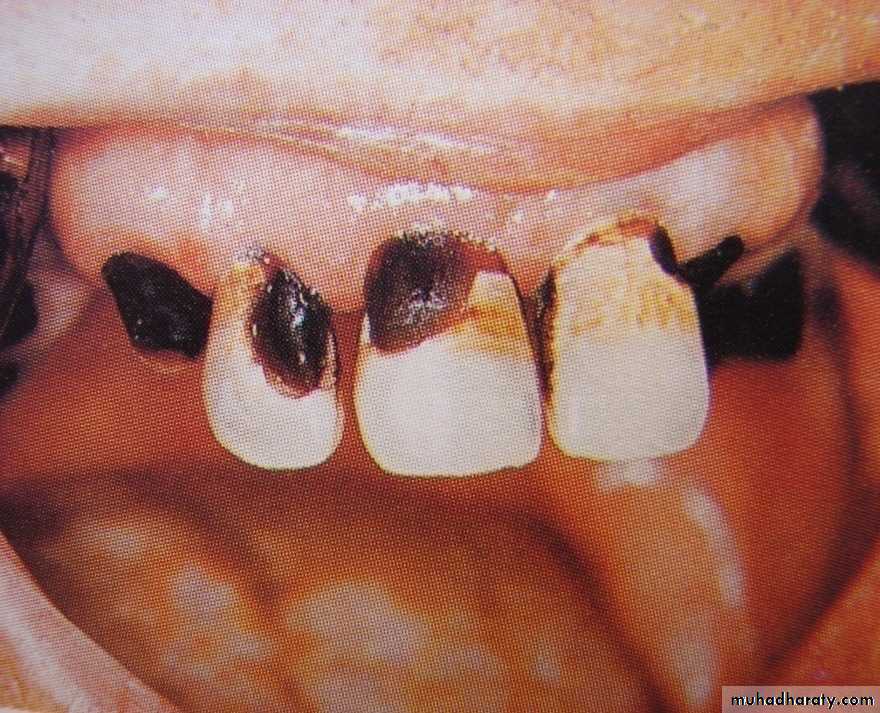

NURSING BOTTLE CARIES

• Nursing bottle containing milk, milk formula or sweetened water.• Breast feeding

• Sugar or honey sweetened pacifiers

Usually, the above aids are used at sleeping time after one year of age.

Clinically seen as widespread caries of the 4 maxillary incisors followed by 1st molars and then canines.Absence of caries in mandibular teeth distinguishes it from ordinary rampant caries.

If milk or other carbohydrates are rapidly cleared from mouth, they aren’t cariogenic, but if they pool in the mouth, then they can cause rampant caries.

Mandibular teeth usually escape the process as the pooled milk or sweet products are washed away by saliva